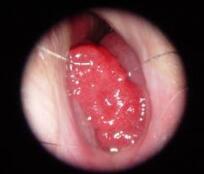

4. 口腔颌面肿瘤:牙源性囊肿、非牙源性囊肿、牙源性肿瘤、肉瘤。涎腺囊肿、皮样囊肿、鳃裂囊肿、血管瘤、淋巴管瘤、乳头状瘤、牙龈瘤,白斑、红斑、扁平苔癣、口腔粘膜恶性黑色素瘤、舌癌、龈癌、腭癌、口底癌、颊癌。

5. 鼻咽癌、喉咽癌、喉癌。